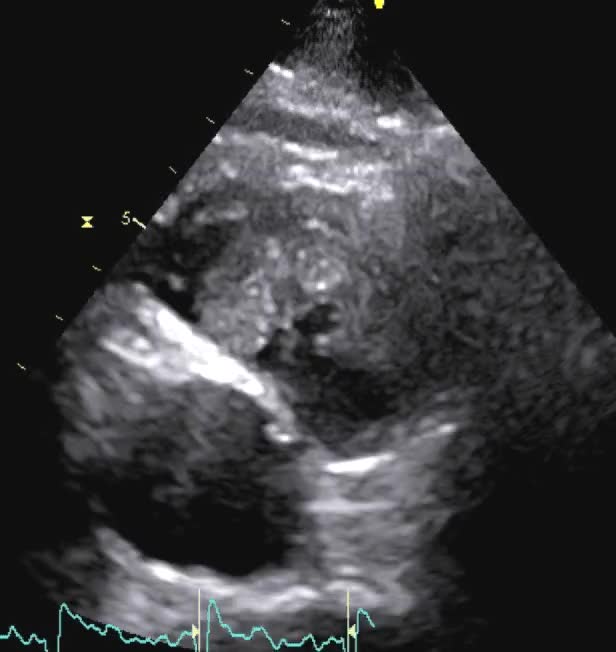

Infarto ventricolare dx

Autore:

Laura Massironi

Titolo: